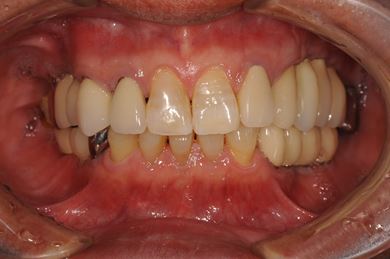

| 性別/年齢 | 男性 / 58歳 | ||||||||||||||||||||||||||||||||

| 主訴 | ブリッジがだめになったため、現在は部分入れ歯を使用しているが、インプラント治療を検討している。 | ||||||||||||||||||||||||||||||||

| 治療方針 | 左上奥の欠損部分をインプラント治療にて、機能的・審美的回復を行う。 | ||||||||||||||||||||||||||||||||

| 治療内容 | インプラント3本(GBR)、ハイブリッドセラミッククラウン3本 | ||||||||||||||||||||||||||||||||

| 総治療費 | 791,520円 | ||||||||||||||||||||||||||||||||

| 治療期間 | 10ヶ月 |